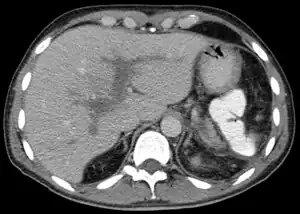

Se o paciente tiver uma pressão elevada na veia porta (hipertensão portal) e o exame microscópico de uma amostra de tecido hepático mostrar que as células estão normais, a trombose da veia porta é o diagnóstico. A ecografia ou uma tomografia axial computadorizada (TAC) podem mostrar a obstrução. O diagnóstico confirma-se mediante uma angiografia, uma técnica de raios X que cria imagens das veias depois de se ter injectado uma substância que causa opacidade na veia porta.[1]